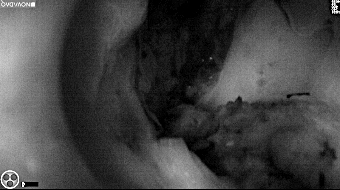

Intraoperative imaging panitumumab-IRDye800 (fluorescence)

Primary tumor prior to resection

Wound bed post re-resection of tumor

Fluorescence imaging of the tumor was performed prior to resection and after resection to “check” the wound bed. In the upper row the tumor is clearly visible with fluorescence and in the bottom row you can see that the wound bed is empty – there is no suspicious fluorescence left. The middle column of tiles show the fluorescence signal in black and white where the “white” represents the tumor and the black the background (= no fluorescence signal). The right column of tiles shows the overlay of the brightfield photo (in greyscale) and the fluorescence (red-yellow-blue heatmap). This image provides anatomical context to the surgeon – the surgeon can see where is the fluorescence located with regard to the tumor area.